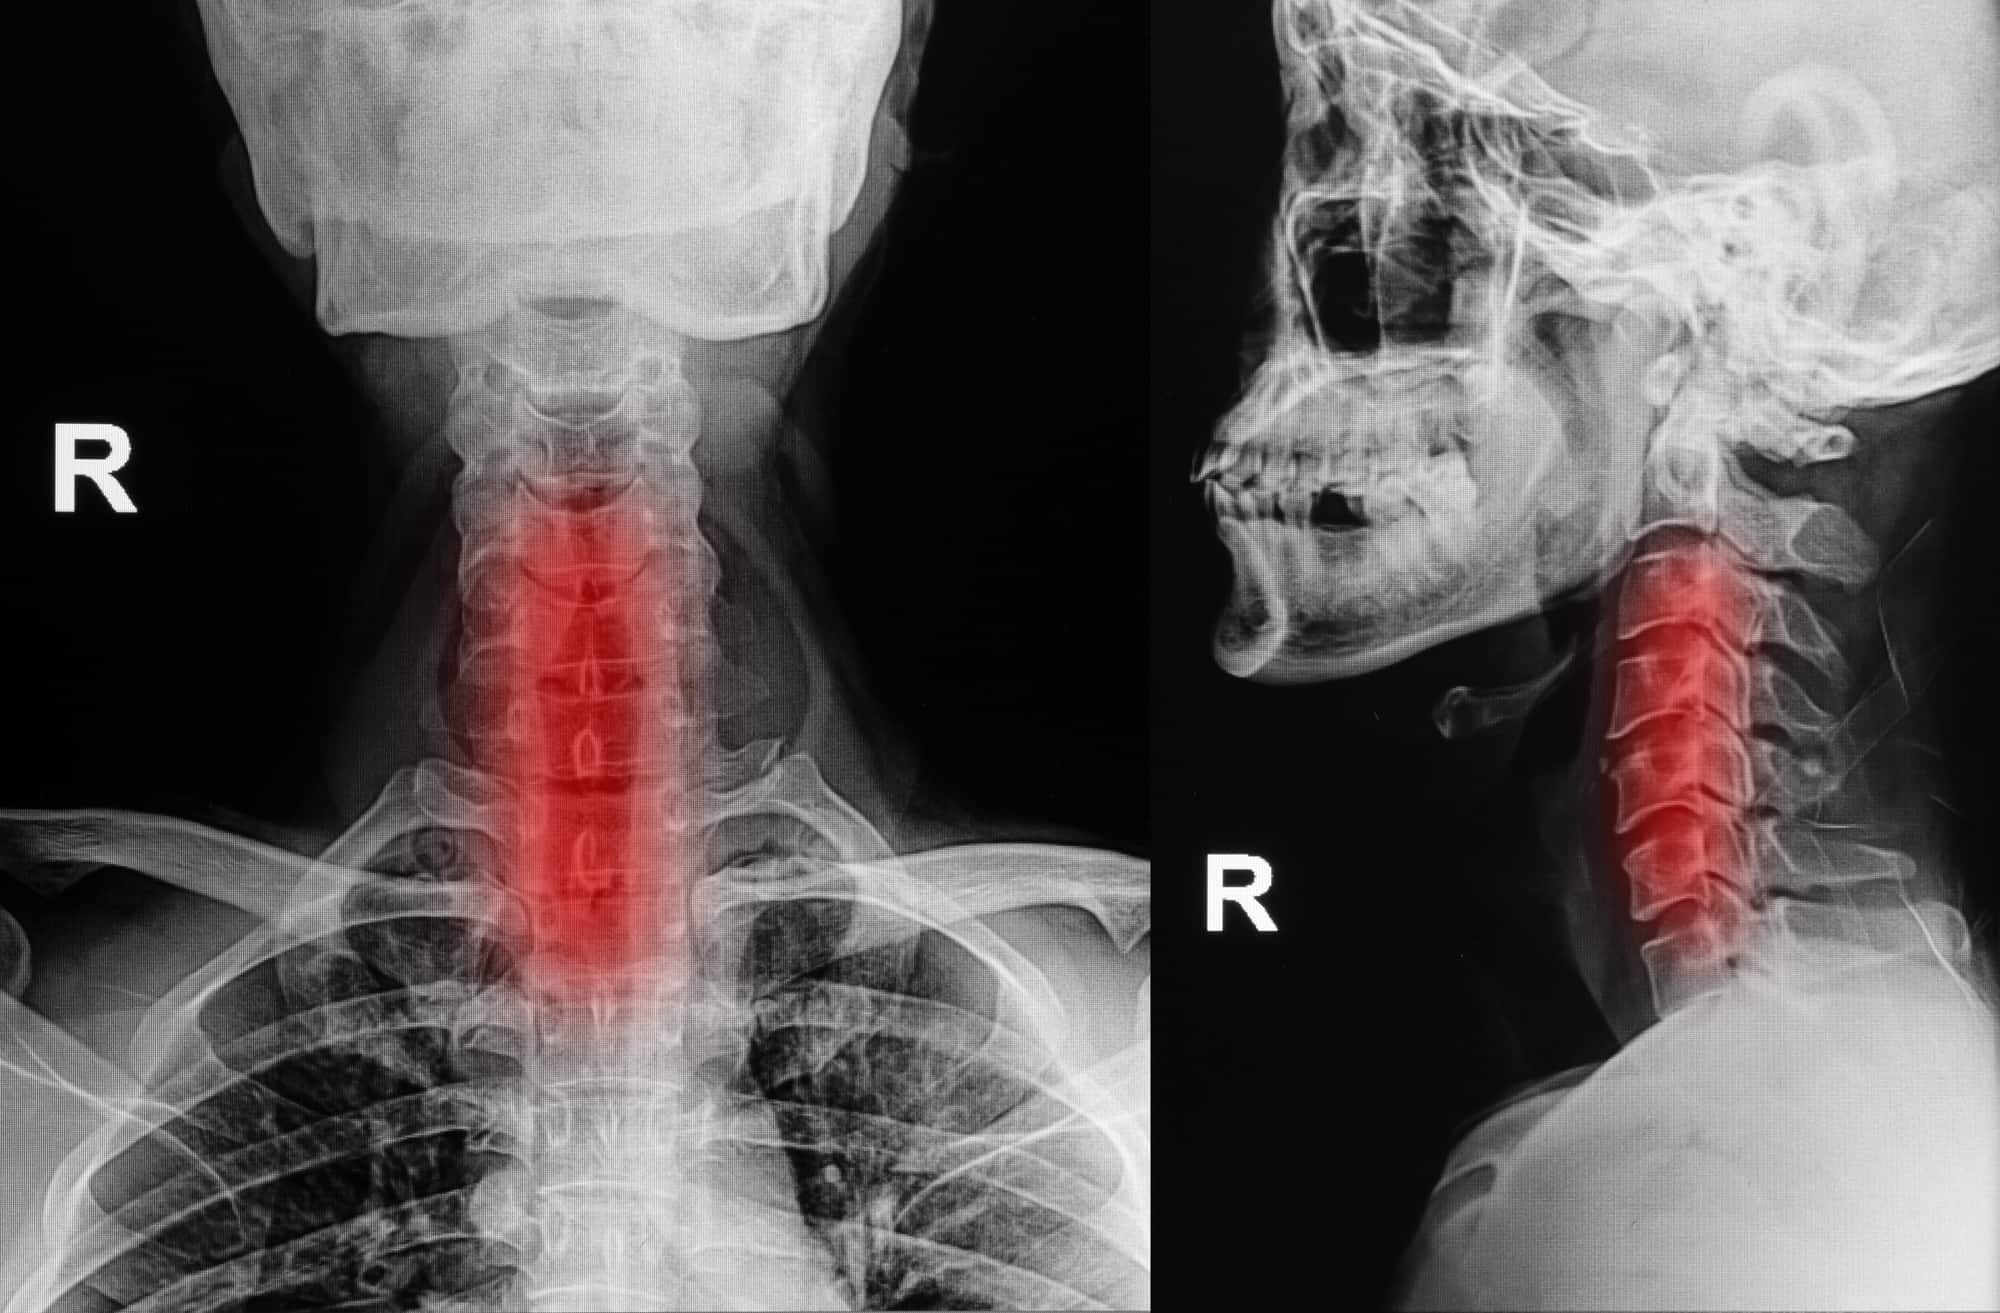

Vôi hóa cột sống cổ là bệnh lý gây đau nhức, hạn chế vận động, ảnh hưởng nghiêm trọng đến sinh hoạt, đặc biệt ở người lớn tuổi. Bệnh xảy ra khi cột sống cổ tích tụ canxi, hình thành gai xương hoặc làm cứng đốt sống. Nếu không phòng ngừa sớm, tình trạng này có thể dẫn đến biến chứng nguy hiểm.

Vôi hóa cột sống cổ là tình trạng tích tụ canxi ở các đốt sống cổ, dẫn đến hình thành gai xương hoặc làm cứng khớp, gây đau nhức và hạn chế vận động. Bệnh thường gặp ở người trên 40 tuổi, nhưng cũng xuất hiện ở người trẻ do lối sống không khoa học.